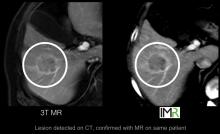

According to a new market research report "Breast Imaging Technologies Market (Digital Mammography,3D Breast Tomosynthesis, Breast MRI, Breast Ultrasound, Molecular Breast Imaging, Optical Imaging, PET/CT/PEM Modalities) Technology and Market Analysis & Global Forecasts to 2017" is an attempt to showcase the market impact of current and emerging breast imaging technologies having excellent growth potential in the coming five years. The technologies profiled in the report are segmented into Ionizing breast imaging modalities and Non-Ionizing breast imaging technologies on basis of radiation. Ionizing breast imaging modalities include Mammography, 3D Breast Tomosynthesis, Cone beam Computed Tomography (CBCT), Positron Emission Mammography (PEM), Molecular Breast Imaging (MBI), Positron Emission Tomography (PET) and Breast Specific Gamma Imaging (BSGI). The various Non-ionizing modalities for breast screening covered in the report are Breast MRI, Optical Imaging, Breast thermography and Breast Ultrasound.